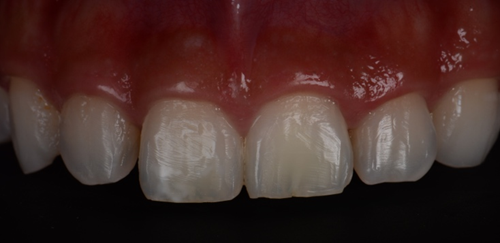

This 22-year-old male came to the clinic complaining of pain and esthetic dissatisfaction following orthodontic treatment. The patient said that his orthodontic treatment lasted more than 4 years. Upon clinical examination, the patient presented with mild to moderate post orthodontic white spot lesions (WSL) affecting the two upper central incisors. Tooth #21 exhibited yellowish discoloration compared to the adjacent teeth due to calcific metamorphosis (Figure 1).

Figure 1. Preoperative frontal photo with a black background to make the contrast better and the white spots more clear